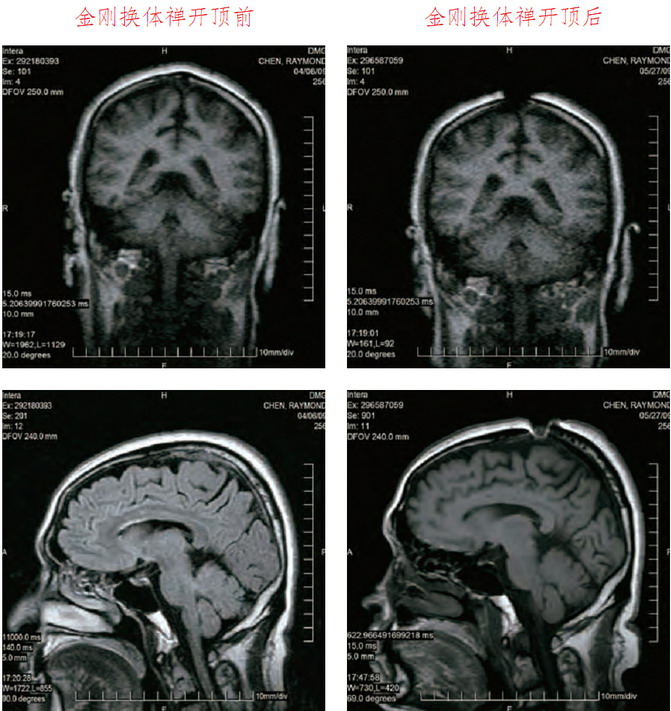

這是祿東贊法王修境行法「金剛換體禪」前後,MRI核磁共振儀腦斷層掃瞄檢測照片。可以清楚看見,開頂後,頭頂大樂輪門處的頭骨、皮層和肉、腦髓裂開約一英吋寬。

祿東贊尊者第四世慈仁嘉措法王開頂成就醫學圖片對比